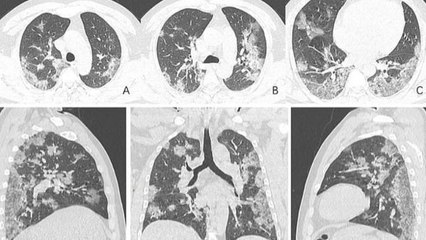

FEMME ACTUELLE -Enrico Macias, touché à son tour par le coronavirus : "Le virus était dans mes poumons"